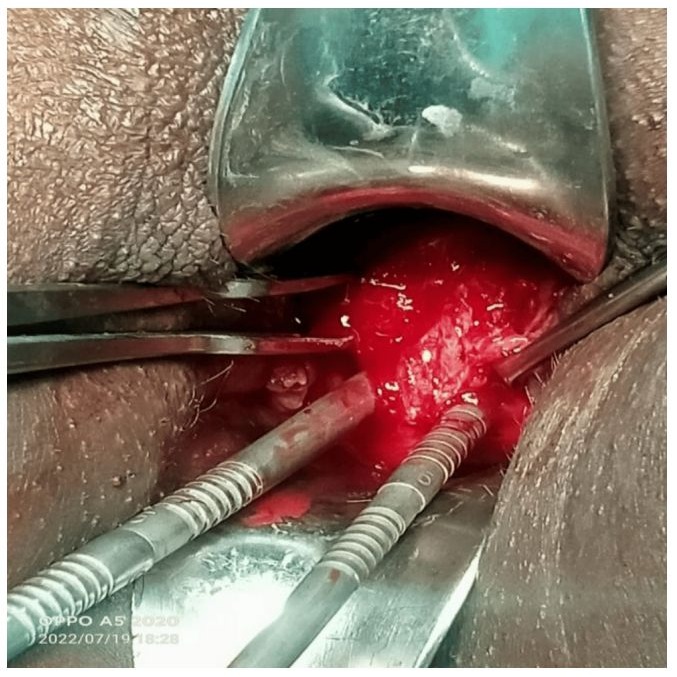

An incision was made on the mass over the right vaginal wall, yielding a discharge of approximately 50ml of pus, which was sent for cytological analysis. Further exploration revealed a vaginal septum that had obscured another cervix. The septum was excised, and dilation of the cervix was performed using dilators. An intra-cervical foly catheter was placed, and the hysteroscopy was repeated.

In conclusion, based on the examination and hysteroscopic findings, the clinical diagnosis was uterus didelphys associated with piccolos due to a right obstructed hemivagina. This obstruction had, by continuity, retrogradely dilatated both hemi-uteri.

Figure 2: Intraoperative finding showing double cervix after excision of vaginal septum